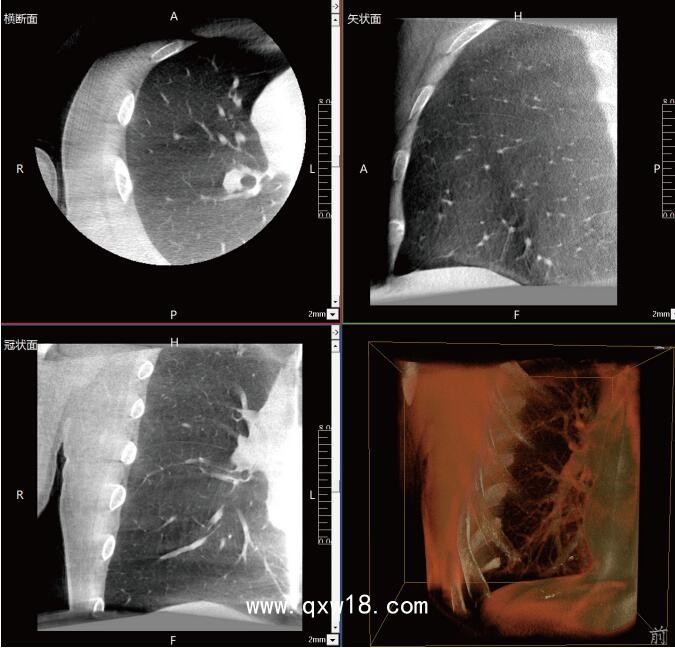

近年來,在肺部手術(shù)領(lǐng)域的應(yīng)用呈現(xiàn)出顯著的增長(zhǎng)態(tài)勢(shì)。這一技術(shù)不僅滿足了臨床指導(dǎo)穿刺、精準(zhǔn)確認(rèn)病變與針尖位置關(guān)系的迫切需求,更通過大量臨床研究的驗(yàn)證,證明了其在肺結(jié)節(jié)診斷、定位及治療中的有效性和安全性。

《中國(guó)專家對(duì)CBCT引導(dǎo)下肺結(jié)節(jié)的診斷、定位和治療的共識(shí)》提到C型臂CT系統(tǒng)憑借其強(qiáng)大的功能,能夠充分滿足透視監(jiān)測(cè)、病變與工具位置確認(rèn)、消融區(qū)監(jiān)測(cè)以及并發(fā)癥檢查等多元化的臨床需求。因此,在考慮設(shè)施條件(如導(dǎo)航設(shè)備、手術(shù)室空間)、靶病灶特性(大小、密度)、麻醉方法及干預(yù)路徑(經(jīng)支氣管或經(jīng)胸)等多重因素的基礎(chǔ)上,C型臂CT系統(tǒng)成為了眾多醫(yī)療機(jī)構(gòu)的優(yōu)選方案。

呼吸介入C型臂CT的臨床適應(yīng)癥廣泛,包括支氣管鏡檢查、肺結(jié)節(jié)穿刺活檢、肺結(jié)節(jié)定位、肺結(jié)節(jié)消融以及經(jīng)支氣管肺結(jié)節(jié)診療等多個(gè)領(lǐng)域。其臨床應(yīng)用價(jià)值不言而喻:在經(jīng)支氣管干預(yù)肺結(jié)節(jié)時(shí),透視功能可精準(zhǔn)引導(dǎo)支氣管鏡與活檢鉗直達(dá)靶結(jié)節(jié);重建的三維圖像則能清晰展示干預(yù)工具的位置,確保操作的準(zhǔn)確性。在肺結(jié)節(jié)消融過程中,呼吸介入C型臂CT更是實(shí)現(xiàn)了高精度定位,有效提升了治療效果。